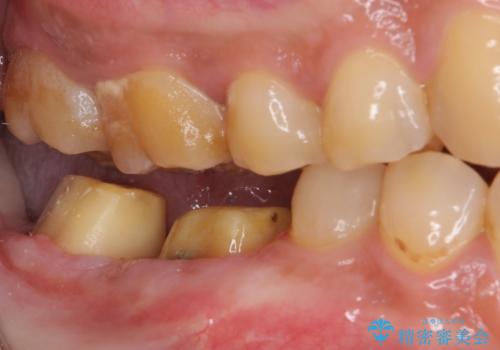

- 親知らずを抜くことが怖く、先送りにした結果親知らずの前の歯に大きな虫歯ができてしまったとのことで来院された患者様です。

親知らずは速やかに抜歯し、手前の歯とその前の歯に歯槽骨にまで及んだ虫歯が認められたため、歯槽骨を削るなどの歯周外科処置を行うこととしました。